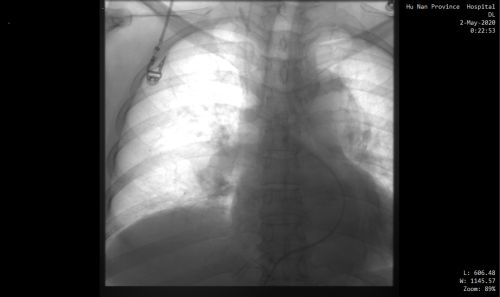

下腔静脉滤器植入前。

情况十万火急,尹新民主任边现场组织抢救,边将情况汇报给向华副院长,向华副院长立即调度全院各相关科室予以协助。一场与生命的赛跑由此拉开!超声科紧急为患者进行床旁彩超,找到肺动脉栓塞的“罪魁祸首”为左下肢静脉血栓。在呼吸治疗组的协助下,医护人员携带转运呼吸机快速运送方女士至介入手术室。介入血管外科紧急安排了手术医生和手术间,由张永琎副主任医师等为患者施行“肺部血管造影”,明确诊断为双肺动脉急性栓塞,随即为其实施“双肺动脉尿激酶冲击溶栓、下腔静脉滤器植入术”。术后,患者肺动脉供血明显改善,血氧饱和度立即回升,被送往重症医学一科继续治疗。